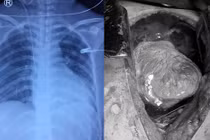

Thông tin từ Khoa Phẫu thuật Tim mạch – Lồng ngực, Bệnh viện đa khoa tỉnh Phú Thọ cho biết, người bệnh bị kéo đâm trúng ngực trái, được đưa vào cấp cứu tại Trung tâm Y tế huyện Cẩm Khê. Tại đây, người bệnh khó thở, mạch nhanh, huyết áp tụt, được xử trí cấp cứu truyền dịch, thở oxy, được chụp CT ngực, siêu âm tim phát hiện có tràn máu màng tim.

Ngay lập tức, các bác sĩ đã hội chẩn trực tuyến với các bác sĩ khoa Phẫu thuật Tim mạch – Lồng ngực, Bệnh viện đa khoa tỉnh Phú Thọ. Chẩn đoán được đưa ra là vết thương tim. Người bệnh được duy trì hồi sức và vận chuyển nhanh chóng đến Bệnh viện đa khoa tỉnh Phú Thọ.

Người bệnh được chuyển đến Bệnh viện đa khoa tỉnh Phú Thọ trong tình trạng khó thở nhiều, da xanh nhợt, mạch khó bắt, huyết áp 90/60mmHg, vết thương thành ngực trái ngang mức khoang liên sườn 5, kích thước 2cm, tiếng tim mờ. Siêu âm cấp cứu tại giường có nhiều dịch máu trong màng tim và màng phổi trái, người bệnh được tiến hành các biện pháp hồi sức và được chỉ định phẫu thuật cấp cứu.

Trong phẫu thuật, các bác sĩ thấy trong khoang màng tim có rất nhiều máu đỏ tươi, khoang màng phổi có 400ml dịch máu đỏ, vết thương rách màng tim thấu vào cơ tim ngay sát động mạch vành phải đã được máu cục bịt lại không còn chảy máu nữa. Các bác sĩ đã lấy máu cục và khâu kín vết thương cơ tim.